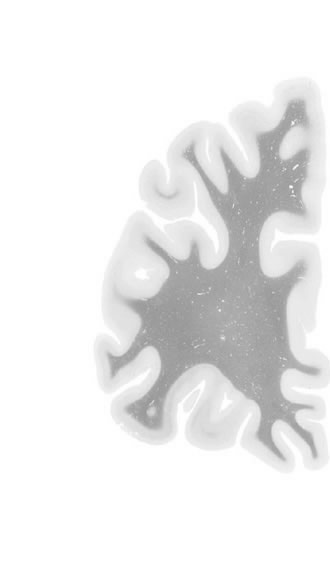

Hi-Resolution Sections · Cells (Nissl Staining) · Virtual Microscopy

Frontal sections (Nissl) from the Atlas Brain:

Macroscopy

Slice ID:

r1-0149

Plate NR:

05

Position:

-37,4 mm